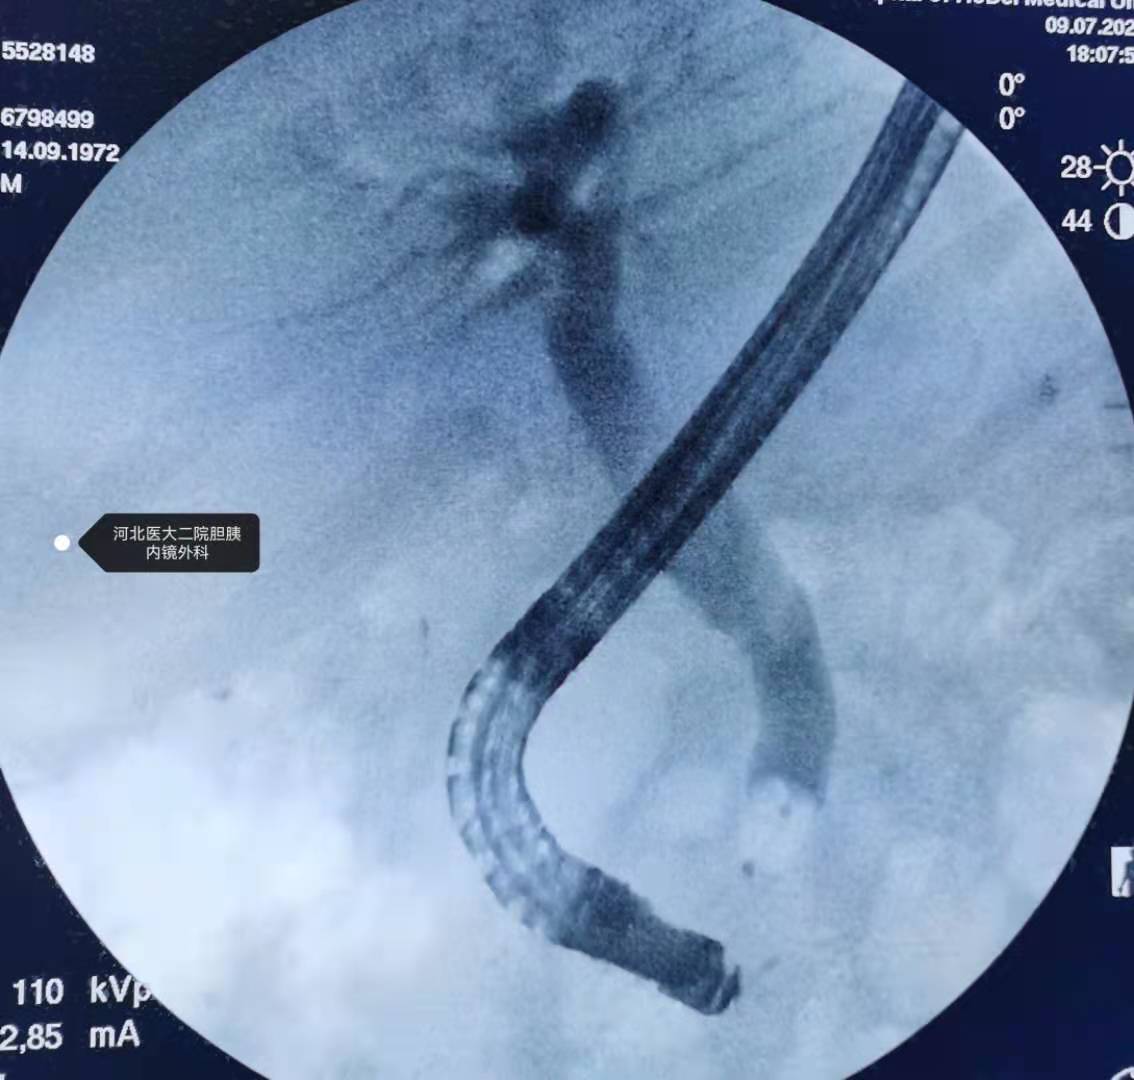

分享一例十二指肠乳头低位开口,憩室内乳头的ERCP取石操作

分享一个十二指肠乳头低位开口(十二指肠水平部),憩室内乳头的,还算顺利。

插管。

镜身已经很弯曲。

造影。